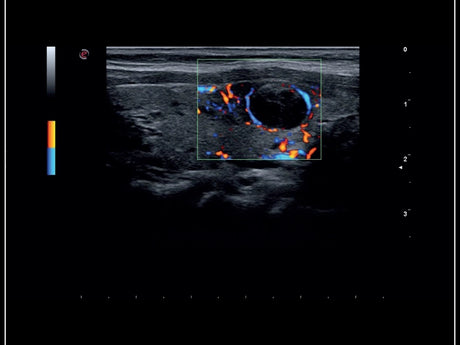

La qualité d’image est au cœur de la philosophie Esaote. Grâce à ses sondes de dernière génération et à son traitement du signal avancé, la marque permet une visualisation fine des structures anatomiques, même les plus profondes. Leurs échographes intègrent des écrans tactiles haute résolution, une interface claire et une connectivité complète, favorisant un flux de travail rapide et efficace.

Les échographes Esaote offrent une restitution d’image d’une grande précision, permettant un diagnostic fiable dans toutes les spécialités. Le traitement numérique optimise le contraste et la netteté, réduisant les artefacts et améliorant la détection des tissus pathologiques. Ces performances sont particulièrement appréciées en gynécologie, où la lisibilité des structures pelviennes ou obstétricales est déterminante.